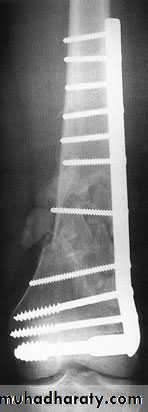

In old internal fixation is often preferable and the patient can get out of bed sooner (dynamic condylar screw and plate) .

dynamic condylar screw and plate

Supracondylar fracture with its fixation by L – plate and screwsComplications